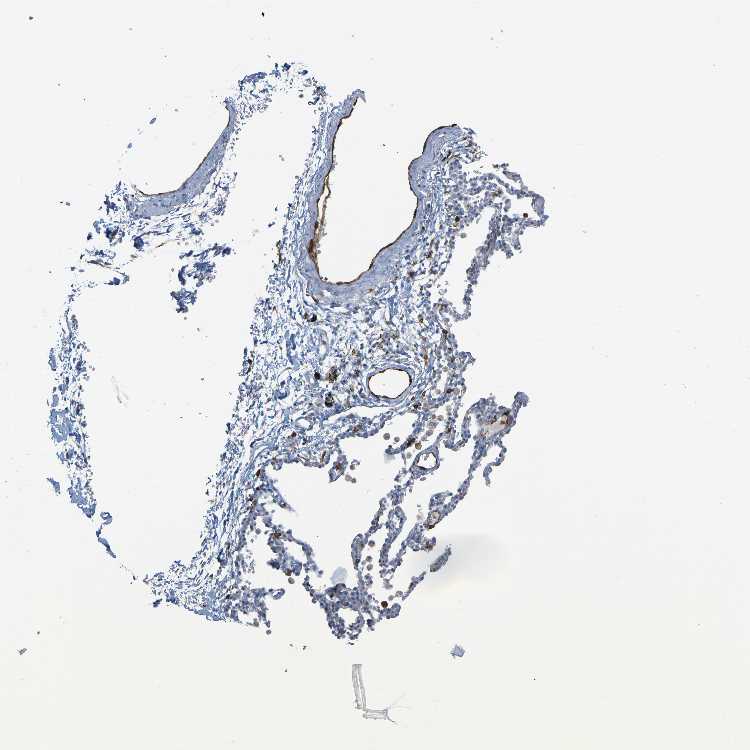

SOFT TISSUE 1 - Antibody stainingi

Antibody staining in the annotated cell types in the current human tissue is reported as not detected, low, medium, or high, based on conventional immunohistochemistry profiling in selected tissues. This score is based on the combination of the staining intensity and fraction of stained cells.

Each image is clickable and will lead to virtual microscopy that enables deeper exploration of all samples and also displays staining intensity scores, fraction scores and subcellular localization as well as patient and tissue information for each sample.

Antibody HPA002834Antibody CAB020315

Fibroblasts Not detectedNot detected

Peripheral nerve -Not detected

SOFT TISSUE 2 - Antibody stainingi

Peripheral nerve Not detectedNot detected